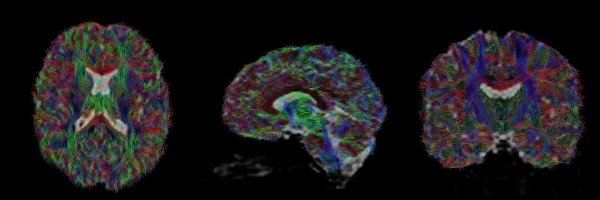

Excited to share the final publication from my PhD! Our findings show microstructural fibre properties of the brain’s white matter do not differentiate recovered children from those with persisting symptoms. 🧠 Paper now available at: https://t.co/Sc1TeRSSsQ

I am excited to share my first paper as lead author published in Journal of Neurosurgery: Pediatrics.🧠 Big thank you to my co-authors in particular - A/Prof Richard Beare, Dr Michael Takagi, Prof Vicki Anderson & Prof Vera Ignjatovic. https://t.co/gkegn2yGJM